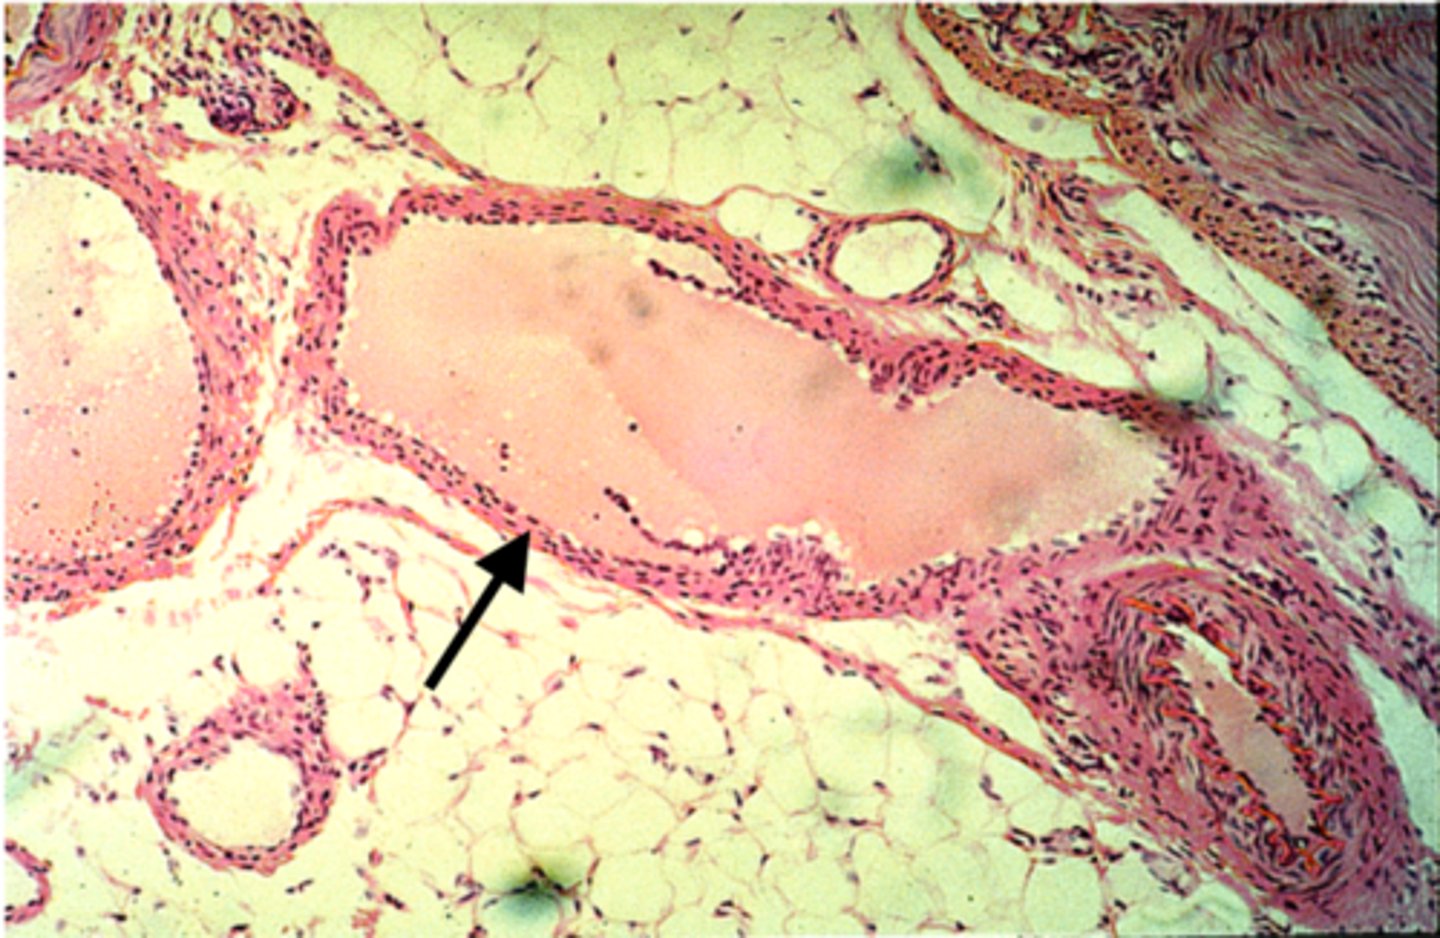

artery

what is this?

vein

what is this?

thicker inner wall

How to identify an artery

thinner inner wall

How to identify a vein